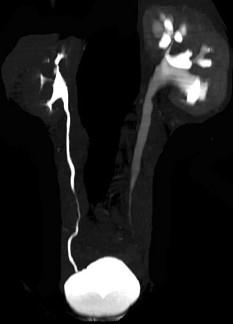

问题 男,59岁,反复尿频尿急尿痛4年余,尿常规检查:红细胞(+),白细胞(++),CT扫描如图示,下列说法正确的是 ( )

选项 A、考虑为慢性输尿管炎 B、考虑为输尿管移行细胞癌 C、左侧侧输尿管上段扩张 D、考虑为输尿管结核 E、左侧输尿管中下段输尿管管壁增厚,管腔狭窄

答案 ACE